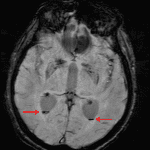

- Trace amount of susceptibility artifact in the occipital horns of both lateral ventricles with a linear ventral margin

- Thin susceptibility artifact along the ventral margin of the medulla

- Intraventricular hemorrhage

Trace intraventricular hemorrhage with blood layering in the occipital horns of both lateral ventricles. No definite evidence of hydrocephalus.

Hemosiderin staining along the ventral margin of the medulla, suggesting sequela of prior hemorrhage.